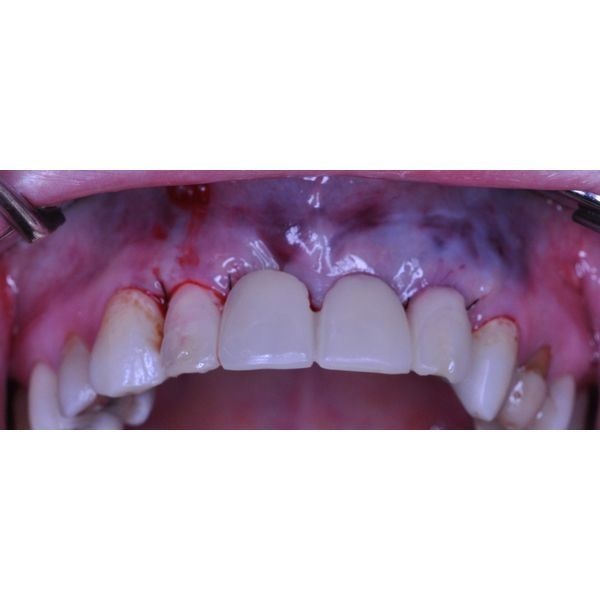

Опорные зубы (1.1, 1.2 и 2.2) разрушены. Сохранившаяся часть зубов была выше десны на 2 мм. Простукивание умеренно болезненно, прощупывание по переходной складке не вызывало дискомфорта. Определялась подвижность II степени (зубы отклоняются чуть больше чем на 1 мм).

Зубы 1.1, 1.2, 2.2 удалили, сразу же установили в раны имплантаты и зафиксировали временный пластмассовый протез. С ним пациентка ходила 5 месяцев.

Ей также смоделировали десневую манжету, на основе чего изготовили циркониевый мостовидный протез с керамической облицовкой.